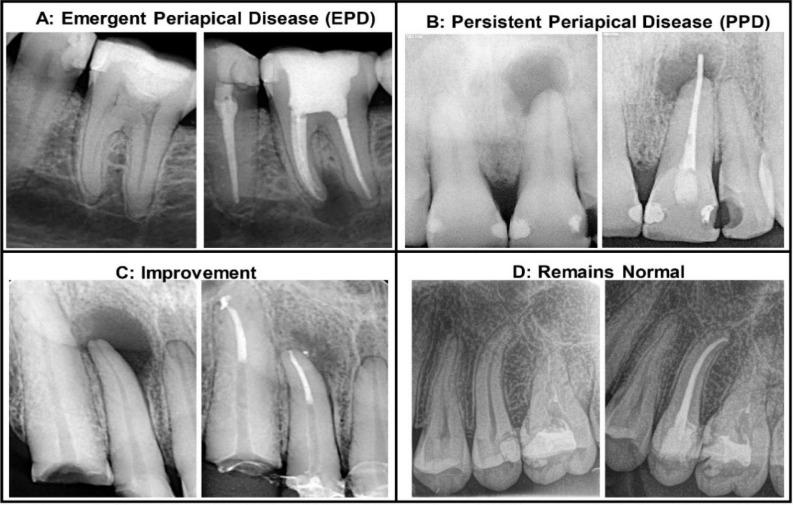

The presented study aimed to characterise periapical disease in teeth with primary non-surgical root canal treatment in persistent or emergent categories and their risk association.

A total of 232 teeth in 155 participants were analysed. A χ2 value, () showed that the emergent disease is associated with patients around the age of 50. The multiple correspondence analysis identified a tendency of grouping between the emergent disease and the short filling category, followed by symptomatic pulpitis as a previous diagnosis. The persistent disease was associated with errors and overfillings. An inadequate root filling and taper density adversely impacted the treatment outcome.

The length of obturation influenced the presence of failure. Short fillings were associated with emerging periapical disease. Errors and overfillings contributed to the persistent disease in the populations studied.